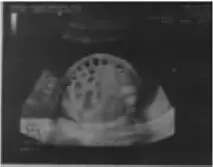

【主訴】因腹瀉3個半月而入院。 【現病史】患兒系第3胎第1產,胎齡34周,因其母孕32周羊水過多胎兒腸管蜂窩狀擴張(圖1)而行剖宮產,出生體重2700g,胎盤及臍帶無異常,羊水無污染,Apgar評分正常。于生后第2天行消化道造影,未發現腸道閉鎖及狹窄。未排胎便,開奶后開始腹瀉,為黃綠色稀水便,水便分離,無黏液及膿血,無發熱及嘔吐。因腹瀉、喂養困難、尿少、精神不振、反應略差而先后3次住院治療,伴有低鉀、低鈉、低氯、代謝性堿中毒,經補液、維持電解質以及酸堿平衡治療后緩解,但是仍有腹瀉,不伴有嘔吐,奶量每次最多70~80ml。可追光追物,可豎頭,俯臥位抬頭欠佳。患兒母親懷孕前兩胎均為妊娠7~8個月因羊水過多而引產。父母非近親結婚,否認類似病史。 圖1 胎兒腹腔內可見腸管擴張,呈蜂窩狀,腸蠕動活躍,羊水指數41.4cm,羊水最大深度121mm。 【查體】